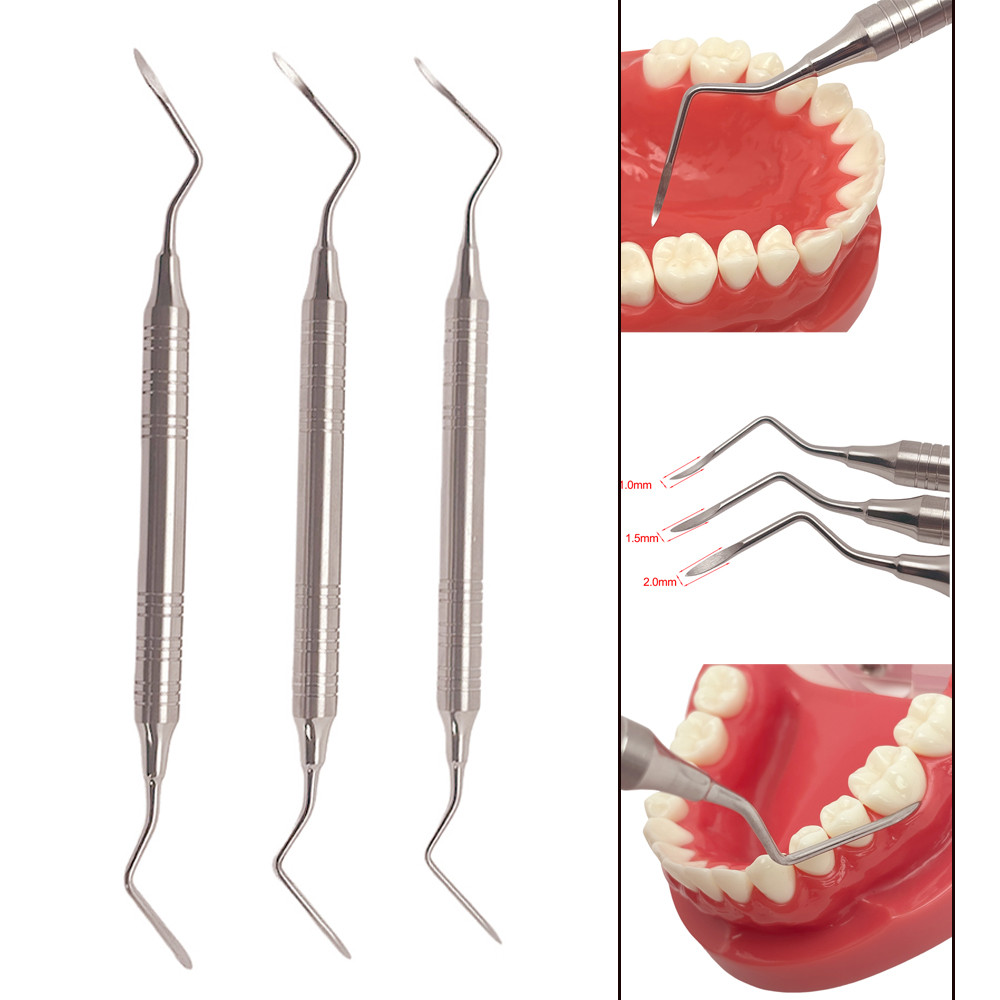

Dental Minimally Invasive Extraction Tool Root Tip Pick Elevator with Sharp Tip for Dental Implant Tooth Extraction Surgical